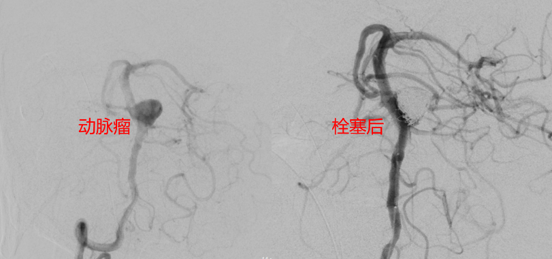

动脉瘤介入栓塞